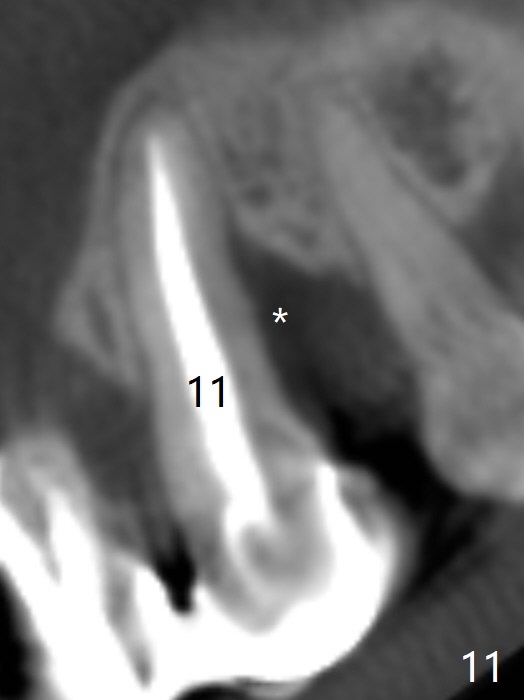

The tooth #10 has severe gingival recession (Fig.1) with loss of the buccal plate (Fig.2 *). After the initial osteotomy depth (Fig.3) increases by 2 mm, a 2.5x14(2) mm 1-piece implant is placed with insertion torque >60 Ncm (Fig.4). Palpation indicates the native bone apparently wider than CT shows. There is no sign of buccal or palatal plate perforation by palpation during osteotomy or implant placement. Vera Graft is placed repeatedly around the coronal threads (Fig.5-7 *). An immediate provisional is fabricated to close the socket (Fig.8). The buccal plate appears to collapse 1 month postop (cortical plate graft apparently more appropriate in this case); the margin of the provisional is trimmed so that the gingiva may grow incisally (Fig.9). The provisional dislodges several times postop due to short abutment. By nearly 4 months postop, the coronal bony defect seems to have been repaired (Fig.10 *). The tooth #11 has tenderness with bone loss (Fig.10 ^), corroborated by CT (distal bone loss, Fig.11 *). Since the apical bone is narrow (Fig.12), a narrow long implant is expected (Fig.13). Use an implant (3.5x13 mm) consistent with those at #14 and 15.